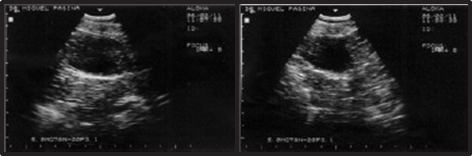

This case involves a 9-year-old female mixed-breed canine, referred for intermittent mild hematuric cystitis. Clinical examination of the abdominal cavity through palpation reveals the presence of a painless, immobile mass with a semi-soft and fixed consistency within the bladder. The ultrasonographic diagnosis reveals the presence of a heterogeneous element with irregular borders and a hypoechoic center, attached to the ventral wall and near the vesical neck, measuring 1.90 cm x 1.85 cm (Figure 1).

Figure 1 Ultrasonographic diagnosis of bladder: Heterogeneous element with irregular borders measuring 1.90 cm x 1.85 cm.

The cryosurgical option was suggested, but the owner declined. Four months later, during a follow-up ultrasound examination, an increase in the mass to 2.90 cm x 2.50 cm was confirmed (Figure 2). Faced with this situation, the owner agreed to the intervention.

Figure 2 Ultrasonographic diagnosis of bladder four months later: Increased mass measuring 2.90 cm x 2.50 cm.